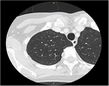

高精度画像診断技術

低侵襲治療に必要な早期発見のため、適切な画像診断検査を行い、微小な病変の発見に努めています。

肺RFA(肺がんに対するラジオ波焼灼治療)

高度組織穿刺技術により、身体にやさしい、新しい肺がん治療法である、肺ラジオ波焼灼治療を行っています。